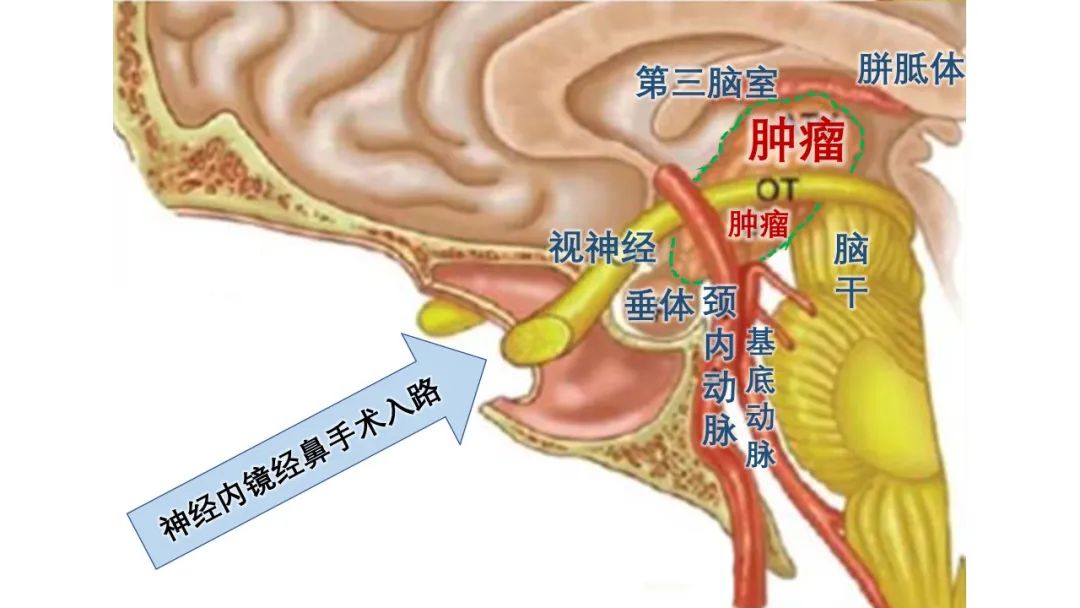

颅咽管瘤是为颅内最常见的先天性肿瘤,好发于颅内中央区域,沿胚胎颅咽管中轴路径生长,紧邻下丘脑、垂体柄、视神经、脑干和颈内动脉等颅内最重要的神经血管结构,主要临床表现有下丘脑-垂体内分泌功能紊乱、颅内压增高、视力及视野障碍,尿崩症以及精神症状。

首选治疗方法为外科手术切除肿瘤,以缓解肿瘤的压迫症状。传统手术方法手术创伤较大,且完全显露并切除肿瘤十分困难。近年来,神经内镜经鼻手术逐渐成为主流,切口位于鼻腔内,可有效减少开颅所致的创伤。但颅咽管瘤经鼻手术需要经过狭小的鼻腔通道,在重要神经血管间隙切除肿瘤,属于最高级别的神经内镜手术之一,难度远高于垂体瘤经鼻手术,且术后易出现下丘脑损伤导致的昏迷不醒、尿崩症、严重水电解质紊乱、垂体内分泌功能危象等严重并发症,极易危及生命或极大降低生存质量。目前在国内仅在少数知名大型综合医院能够独立完成该手术治疗。

颅咽管瘤解剖结构及手术入路

杨先生的颅咽管瘤具体分型为鞍上漏斗结节下丘脑型,肿瘤直径3cm,已生长入第三脑室内,被下丘脑及垂体柄漏斗部包绕,为经鼻内镜手术中治疗难度最高的类型。颅底内镜团队在术前采用三维影像重建等方式,联合内分泌科、影像科、眼科、危重医学科等多学科讨论研究后,为患者量身定制精心设计了内镜手术及综合治疗方案。